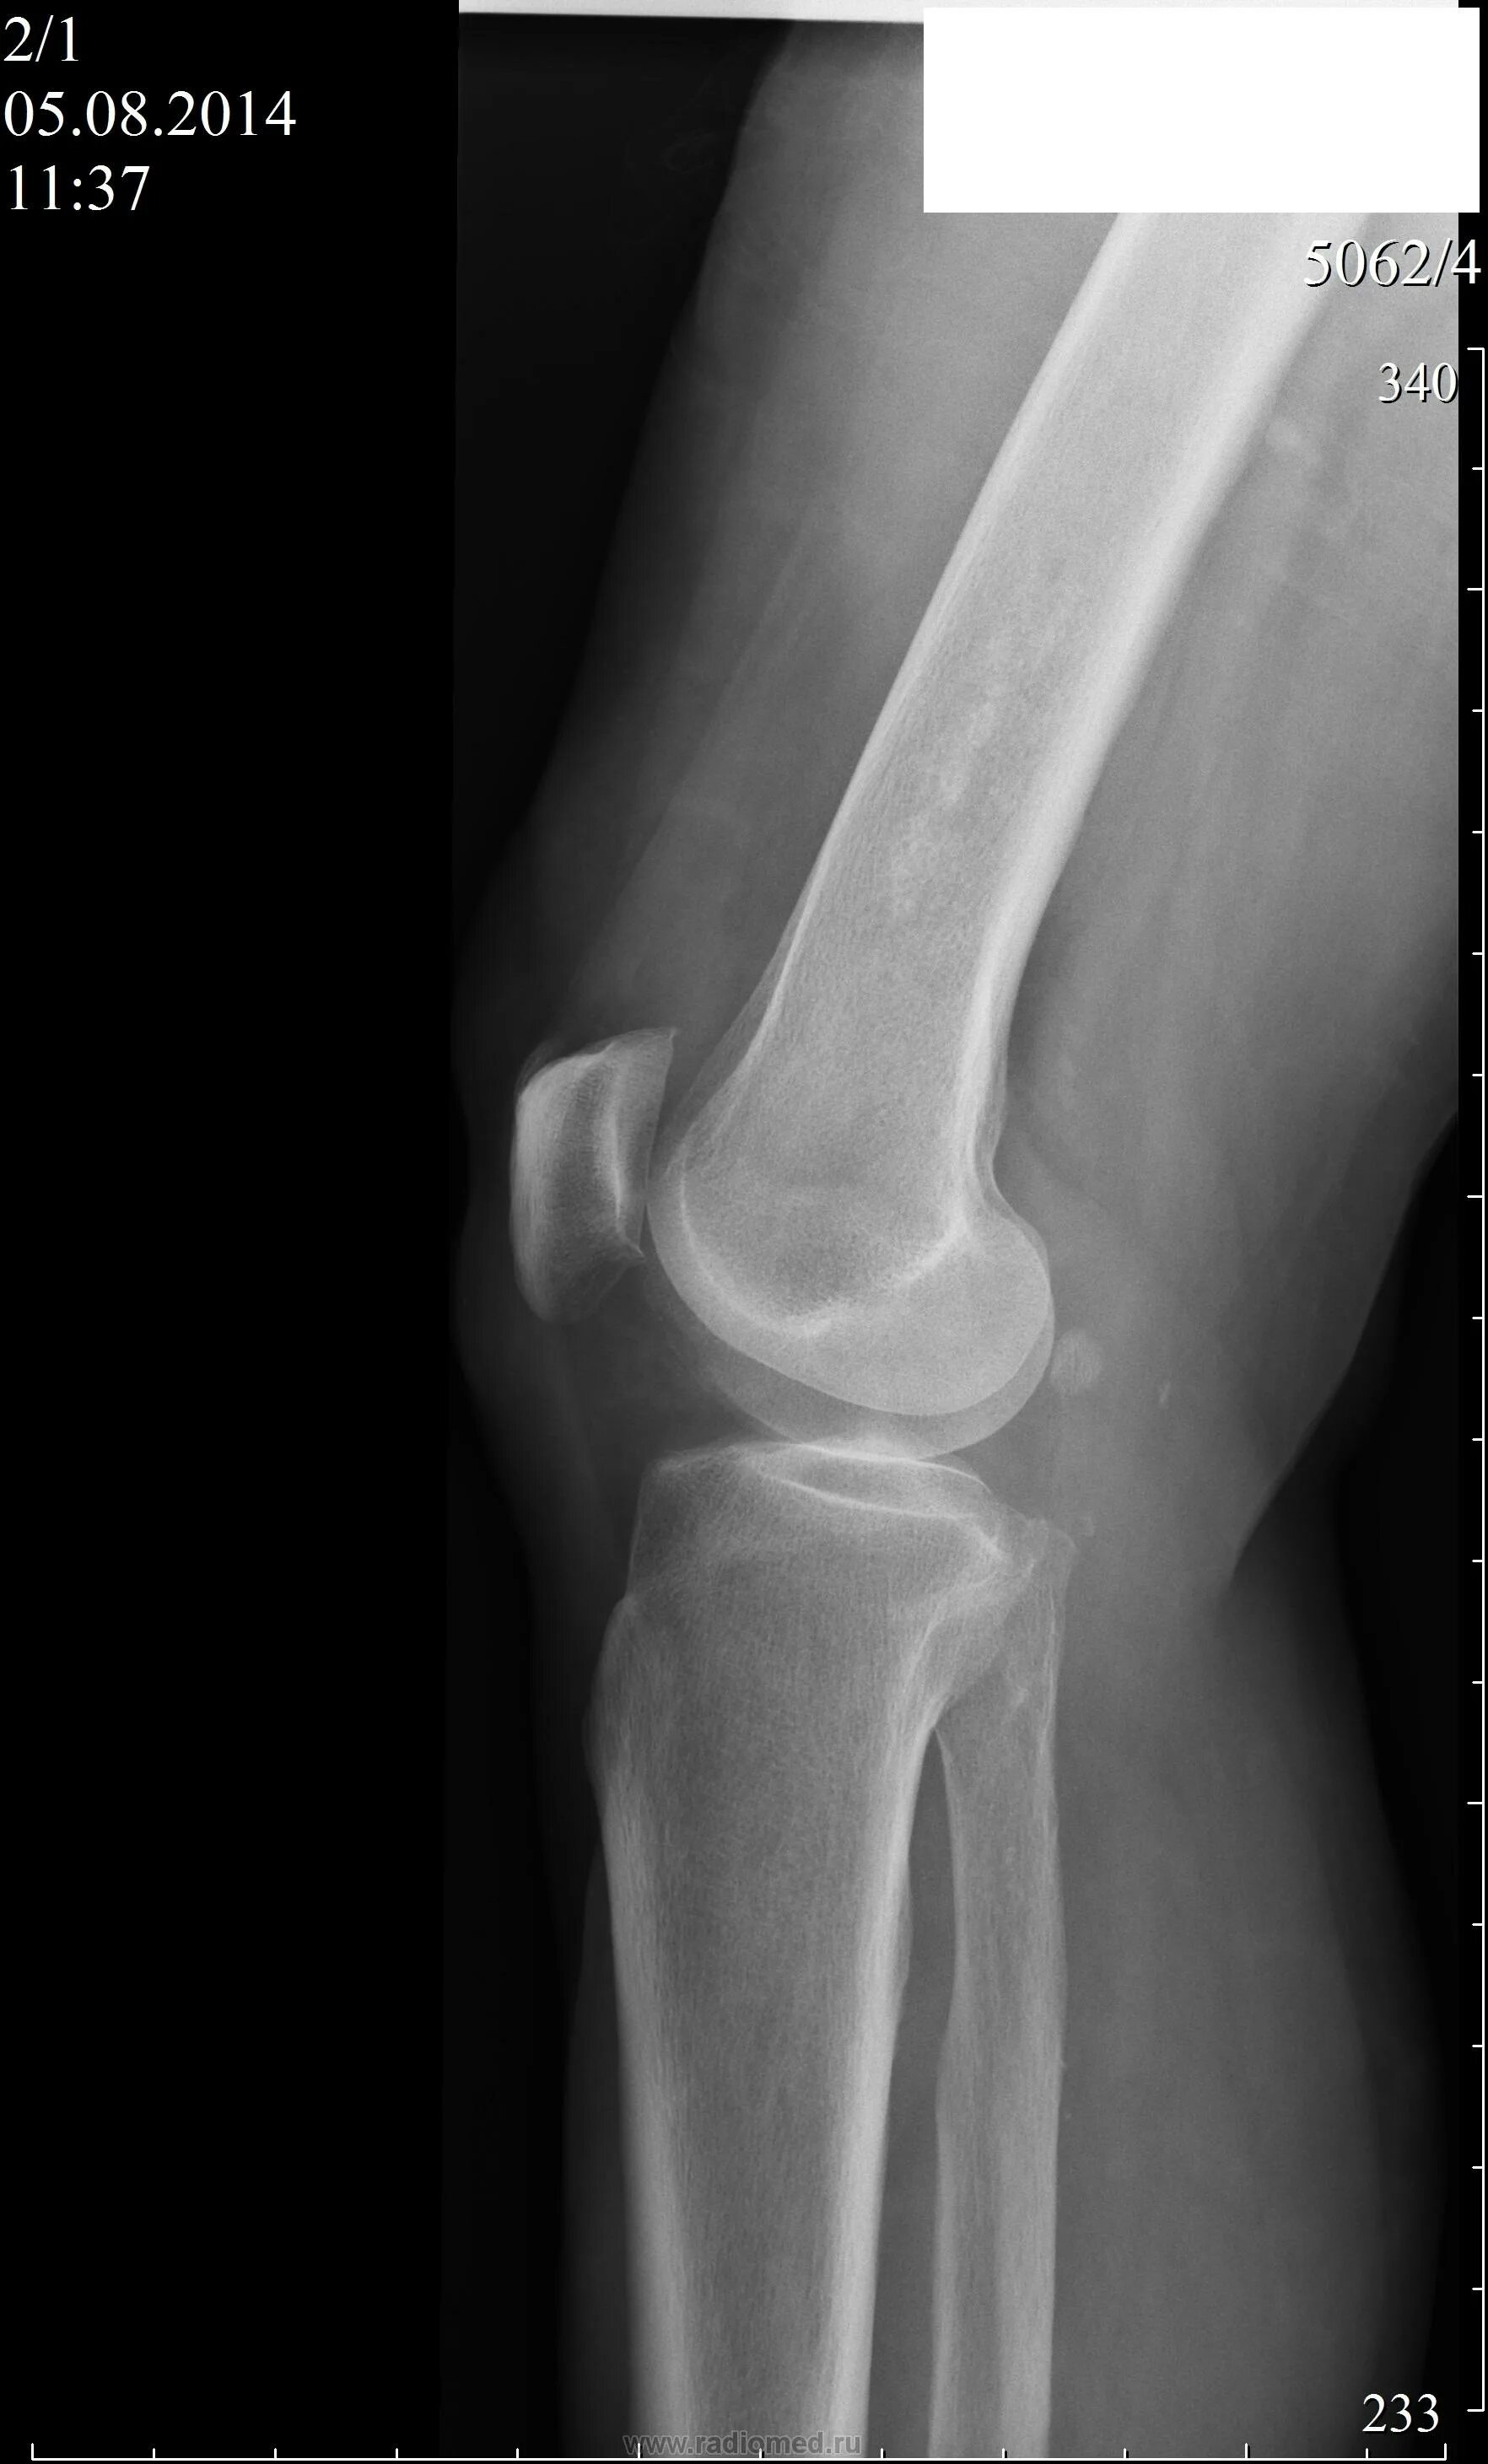

Рентгенография коленного сустава 2 проекции